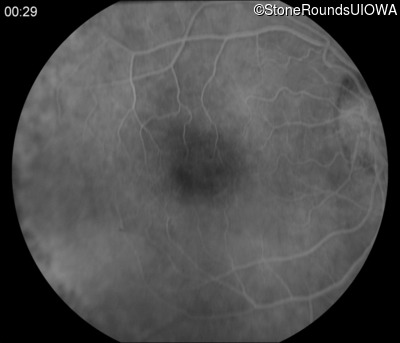

Fluorescein Angiography - Right - 20/50 +2

Exemplar

Fluorescein Angiography - Left - 20/160